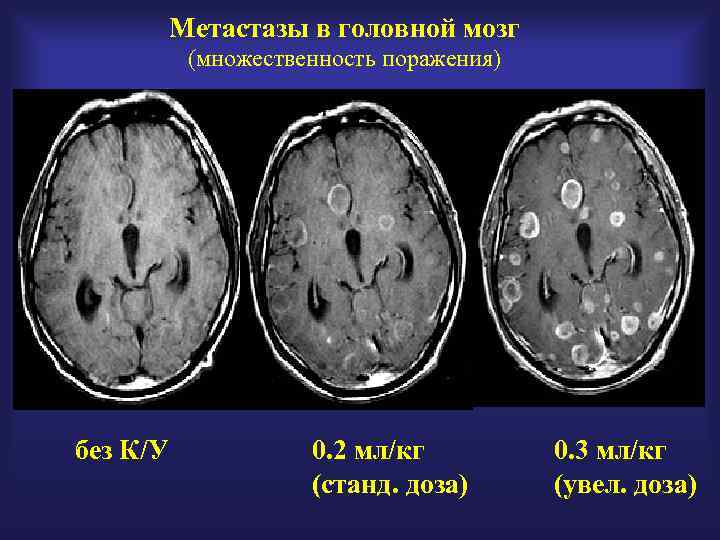

Метастазы в головной мозг (множественность поражения) без К/У 0. 2 мл/кг (станд. доза) 0. 3 мл/кг (увел. доза)